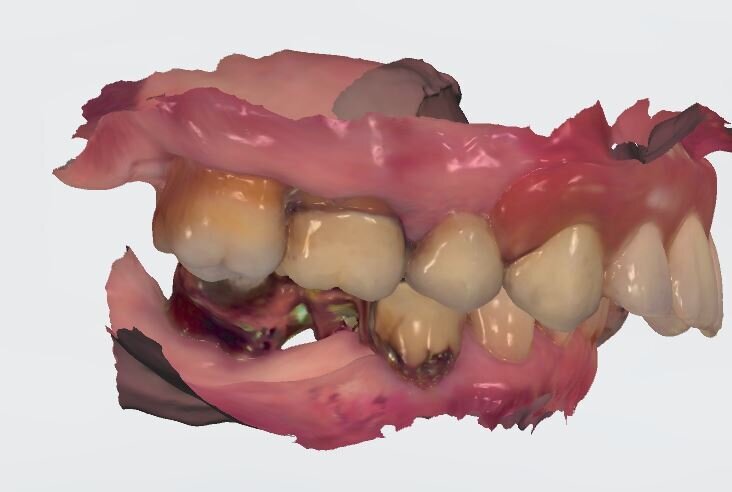

È auspicabile un’approccio multidisciplinare in casi clinici così complessi, prevedendo un’attenta fase iniziale diagnostica clinico-radiologica ed estetico funzionale. Dopo un primo sondaggio degli elementi residui e una radiografia panoramica abbiamo eseguito un’impronta studio tramite uno scanner intraorale, il cui file estrapolato è stato condiviso con il laboratorio per eseguire un wax-up diagnostico successivamente condiviso con la paziente. La tipologia del restauro da eseguire ha richiesto l’intervento su entrambe le arcate dentarie, escludendo un trattamento intercettivo precluso a priori dalla paziente e lasciando inalterato lo stato del V° sestante.

Per un’analisi completa in casi così compromessi è necessario il maggior numero di informazioni che dovranno essere raccolte partendo dal confronto con la paziente per quelle che sono le abitudini alimentari, la sua attività lavorativa, gli interessi sociali. Tutto ciò permette di capire quanto la paziente si aspetti dal nostro intervento ponendo la giusta attenzione all’estetica oltre che alla naturale funzione, è altresì importante rilevare delle immagini con e senza la protesi provvisoria in situ (Fig. 2). Nonostante si evinca la mancanza di congruità del manufatto protesico con la cresta residua la paziente ha mostrato difficoltà nel concepire una sua sostituzione per il timore di un peggioramento estetico. Il supporto di un progetto digitale ha consentito alla paziente di capire quale risultato potesse raggiungere a percorso ultimato. È evidente il collasso che il labbro superiore subisce quando viene rimossa la protesi con la rappresentazione del “codice a barra” dato dalla mancanza dei denti e della struttura ossea sottostante (Figg. 3, 4), a tal scopo è consigliabile poter fotografare la paziente nel profilo in entrambe le situazioni così da far emergere le discrepanze, anche nell’impronta digitale rilevata è importante acquisire il maggior numero di informazioni (Fig. 5).

L’informazione diagnostica dettagliata è fornita dalla CBCT, pertanto abbiamo pianificato la sua esecuzione dopo la prima provvisorizzazione dell’arcata superiore evitando lo scattering da metalli presenti. Il file STL del wax-up (Fig. 6) associato al file STL dell’impronta senza provvisorio (Fig. 7) e al file DICOM radiologico (Figg. 8, 9) ha permesso una corretta progettazione chirurgico implantare (Fig. 10) nel rispetto della porzione ossea della cresta residua, ottimizzando la conseguente realizzazione della dima chirurgica (Fig. 11) per il posizionamento degli impianti in sede 1.2 e 2.2 (Figg. 12-14) anche nel rispetto della posizione degli elementi in antagonismo (Fig. 15). Il primo provvisorio avrà diverse funzioni tra cui la valutazione dell’inclinazione coronale, l’ingombro volumetrico e il supporto labiale del gruppo frontale per la correzione dell’emergenza del labbro superiore (Fig. 16). Dopo un breve periodo di stabilizzazione funzionale di almeno due mesi, si valutano i movimenti mandibolari, masticatori, il ripristino dei tessuti parodontali e il condizionamento biologico degli elementi intermedi. Nello specifico del caso trattato abbiamo evidenziato subito un collasso della masticazione associato a un morso profondo che non avrebbe consentito alcuna protesizzazione degli elementi mancanti (Fig. 2). Pertanto abbiamo dovuto realizzare un rialzo di masticazione anche per correggere l’emergenza degli elementi sostitutivi. La preparazione degli elementi residui concepita ha eliminato tutti i materiali che avrebbero creato un disturbo nell’indagine radiologica (Fig. 17).